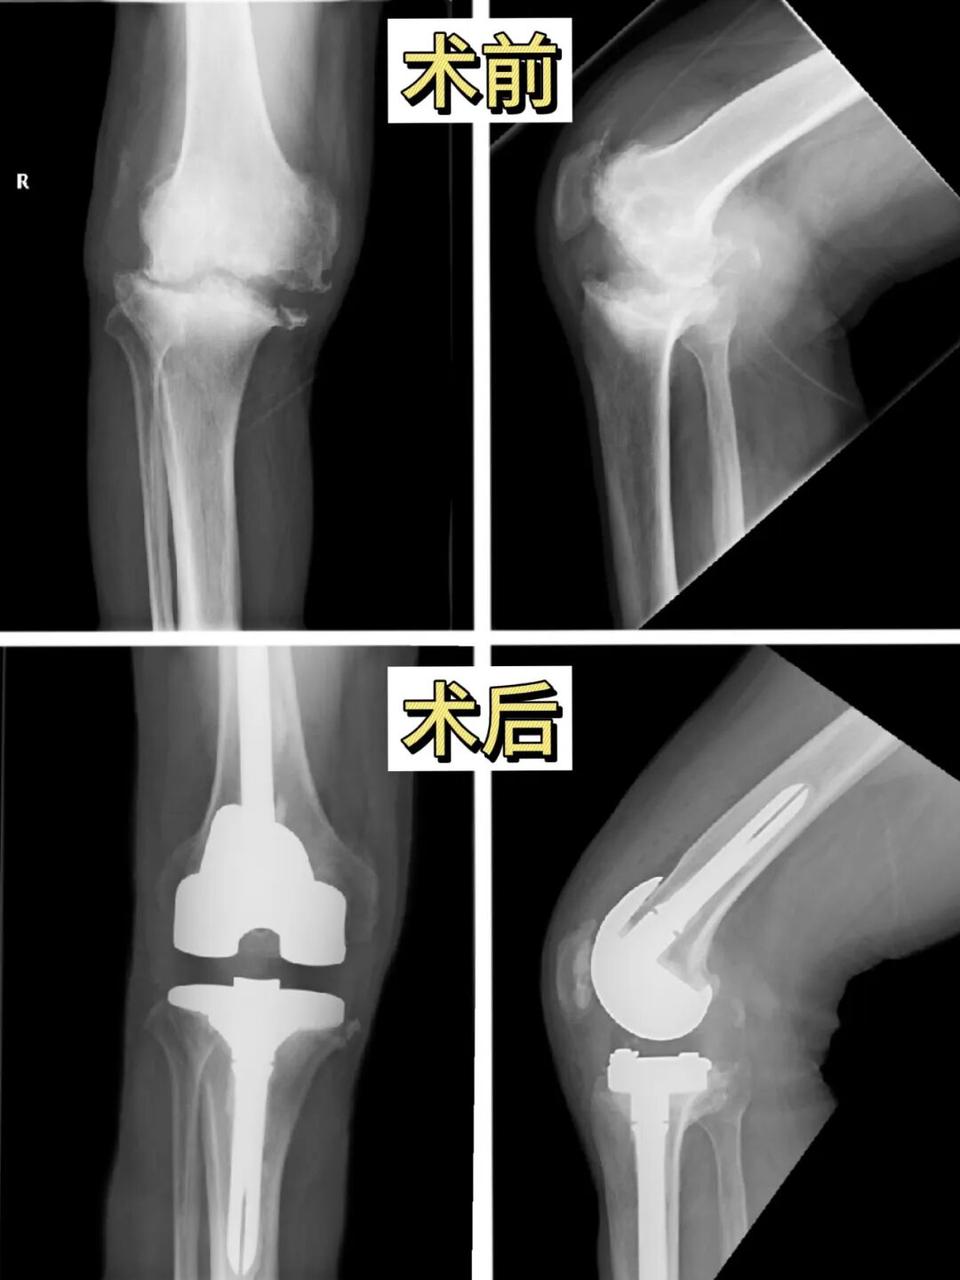

In less than four months, more than 100 knee replacement surgeries were successfully performed.

This is the latest achievement delivered by Professor Li Jun, Chief Orthopedic Specialist of HCHORIZON, together with the orthopedic team at Pizhou Dongda Hospital, which includes multiple complex cases such as severe flexion contracture deformities.

• Enhanced capacity to manage complex cases: Knee flexion contracture surgery, which requires advanced techniques in soft tissue release and flexion-extension gap balancing, has historically been less common in county-level hospitals. The team’s success demonstrates its technical readiness to handle complex cases.

As diagnostic and treatment capabilities have improved, patients from surrounding counties and cities have increasingly sought care at the hospital. Recently, a patient from Henan Province traveled specifically to Pizhou Dongda Hospital to undergo CCK artificial knee replacement surgery.